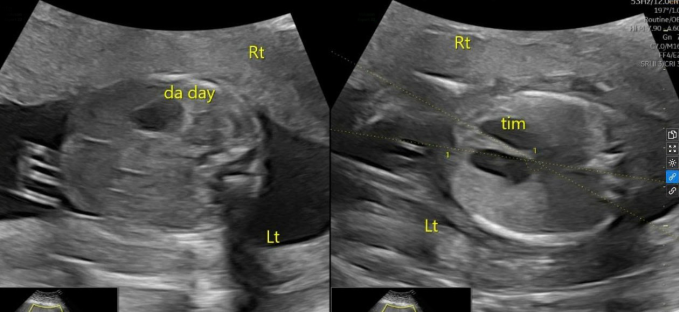

Ảnh siêu âm cho thấy tim và dạ dày của thai nhi nằm ở bên phải. Ảnh: Phòng khám Đa khoa Tâm Anh Quận 7

Mẹ bé, 29 tuổi, theo dõi ba tháng đầu thai kỳ tại phòng khám tư ở địa phương không ghi nhận bất thường, sàng lọc tiền sản giật nguy cơ cao và được dự phòng bằng thuốc Aspirin. Ở tuần thai thứ 20, chị đến Phòng khám Đa khoa Tâm Anh Quận 7, ThS.BS Nguyễn Thị Liên Phương, chuyên khoa Y học bào thai, siêu âm phát hiện tim và dạ dày thai nhi nằm ở bên phải cơ thể (bình thường ở bên trái), biểu hiện của đảo ngược phủ tạng. Đây là tình trạng các cơ quan trong cơ thể nằm ngược lại so với vị trí giải phẫu bình thường.